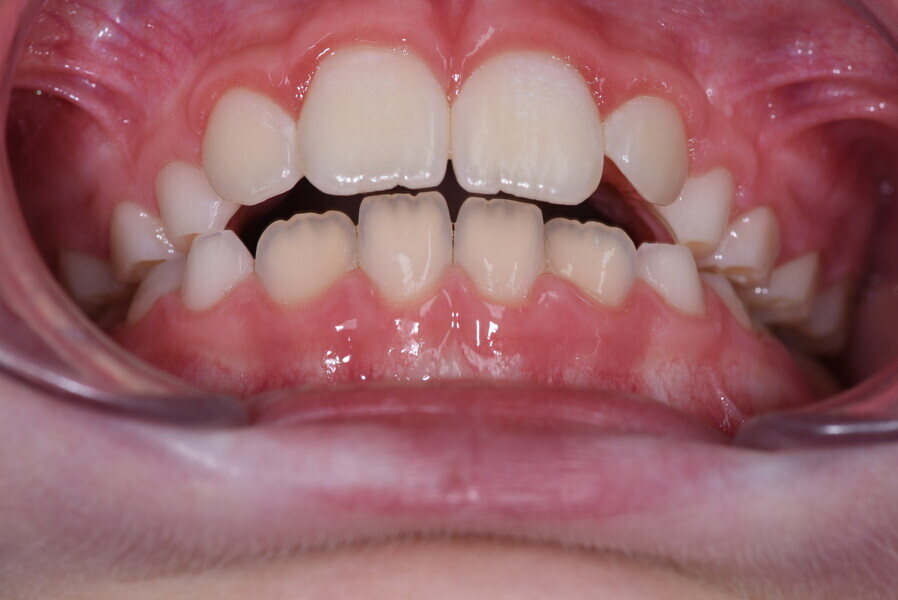

The 58-year-old patient wished to improve his oral aesthetics and function, complaining of mobility of the posterior teeth and wear of the anterior teeth. After data collection, a very complex situation was identified (Figs. 11–13):

1. severe periodontitis with poor prognosis of some teeth;

2. anterior crossbite;

3. severe wear mainly of the anterior teeth and compensatory eruption;38

4. atypical swallowing and lower posture of the tongue at rest;

5. masticatory dysfunction during the mastication test; and

6. no significant signs of temporomandibular disorder.

After the first phase of aligner treatment, we had achieved better inter-arch coherence, better maxillary arch expansion, and some space for improving the anterior tooth proportions restoratively (Fig. 19). We then temporarily restored the anterior teeth directly with composite, closing the spaces, improving the tooth proportions and further increasing the maxillary arch expansion (Fig. 20). We used restorative arch expansion to reduce the orthodontic destabilisation of the teeth to achieve the correct inter-arch coherence and retain the teeth in the cortical bone.38 A refinement aligner phase was undertaken to improve the final alignment of the gingival zenith and to improve the inter-arch coherence (Fig. 21). The periods of the first orthodontic phase and of the refinement were used to augment the mandibular and maxillary bone and to place the implants (Fig. 22). At the end of the orthodontic treatment, the case was finalised with ceramic veneers in the anterior area and temporary restorations on the implants in the posterior area (Figs. 23–26).